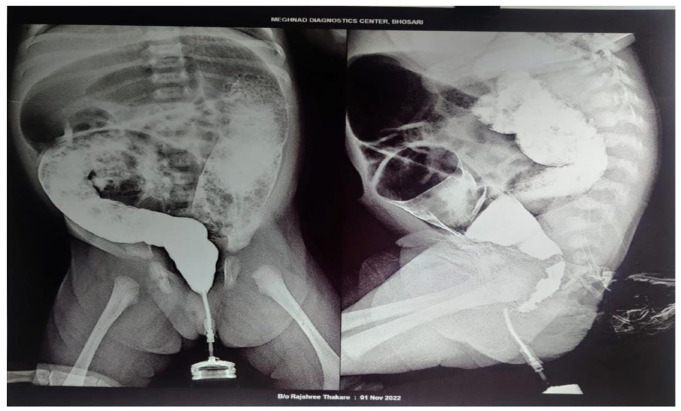

赫氏病是一种先天性疾病,其特点是结肠肌肉神经细胞缺失,导致排便困难。本病例报告描述了一名新生儿患者的典型症状,包括腹胀、便秘、腹泻和发热。患者最初的实验室检查结果显示贫血(血红蛋白:9.80 g/dL)、红细胞计数低(350 万/立方毫米)、RDW 升高(16.70%)、白细胞计数升高(11 000/立方毫米)、血小板水平升高(891 000/微升)以及 CRP 升高(3.22)。婴儿接受了综合治疗,包括输血、Syp.MVBC, Enterogermina, Inj.Pan, Inj.Metro、Inj.Piptaz, Inj.万古霉素、葡萄糖酸钙和 Inj.阿米诺文。经过治疗和必要的手术干预后,患者频繁排便的情况明显改善,其他症状也有所缓解。本病例强调了及时诊断和多学科治疗对婴儿赫氏贲门失弛缓症患者获得良好治疗效果的重要性。

Hirschsprung's disease is a congenital disorder characterized by the absence of nerve cells in the colon muscles, leading to difficulties in evacuating stool. This case report describes a newborn patient presenting with typical symptoms of the disease, including abdominal distension, constipation, diarrhea, and fever. The patient's initial laboratory investigations revealed anemia (Hb: 9.80 g/dL), low RBC count (3.50 million/cu mm), elevated RDW (16.70%), increased WBC count (11 000/cu mm), and raised platelet levels (891 000/µL) along with an elevated CRP (3.22). The baby received a comprehensive treatment regimen, including blood transfusion, Syp. MVBC, Enterogermina, Inj. Pan, Inj. Metro, Inj. Piptaz, Inj. Vancomycin, Calcium gluconate, and Inj. Aminoven. Following this treatment and necessary surgical intervention, the patient demonstrated significant improvement in frequent bowel movements and alleviation of other symptoms. This case highlights the importance of prompt diagnosis and multidisciplinary management for favorable outcomes in infants with Hirschsprung's disease.